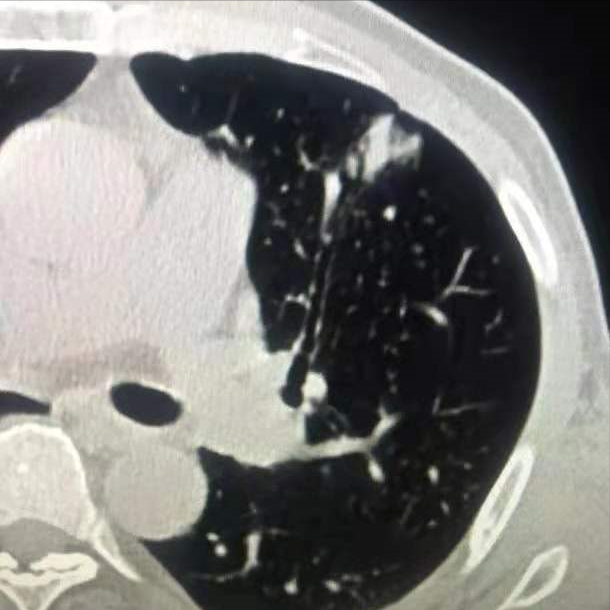

一个网友帮母亲咨询 , 他的母亲常规体检胸部CT查出肺部结节 , 病灶才2cm , 穿刺活检提示腺癌 , 中-低分化 。 就在全家庆幸病灶不大准备手术时 , 做脑部磁共振检查发现脑部转移了 。 这个结果令他无法接受 , 一再的追问 , 肺腺癌真的转移这么快吗?

肺腺癌是肺癌的一种 , 属于非小细胞肺癌 。 一般起源于支气管粘膜上皮 , 少数起源于大支气管的粘液腺 。 腺癌细胞不规则、核仁明显、胞浆丰富、常含黏液 , 是肺癌中最常见的类型 。 由于大多数腺癌起源于较小的支气管 , 一般病灶处于肺周边 , 为周围型肺癌 。 早期一般没有明显的临床症状 , 往往在胸部CT检查时被发现 , 表现为类圆形或椭圆形肿块 。

总之 , 腺癌和鳞癌最大的区别在于 , 腺癌容易发现早期转移 。 即使肺部病灶比较小 , 但是在确诊时可能已经出现了全身其他脏器转移 。 鳞癌虽然在局部容易形成比较大的肿块 , 形成阻塞性肺炎并合并有肺出血等情况 。 但是其生长速度比较慢 , 转移的速度也比较慢 。